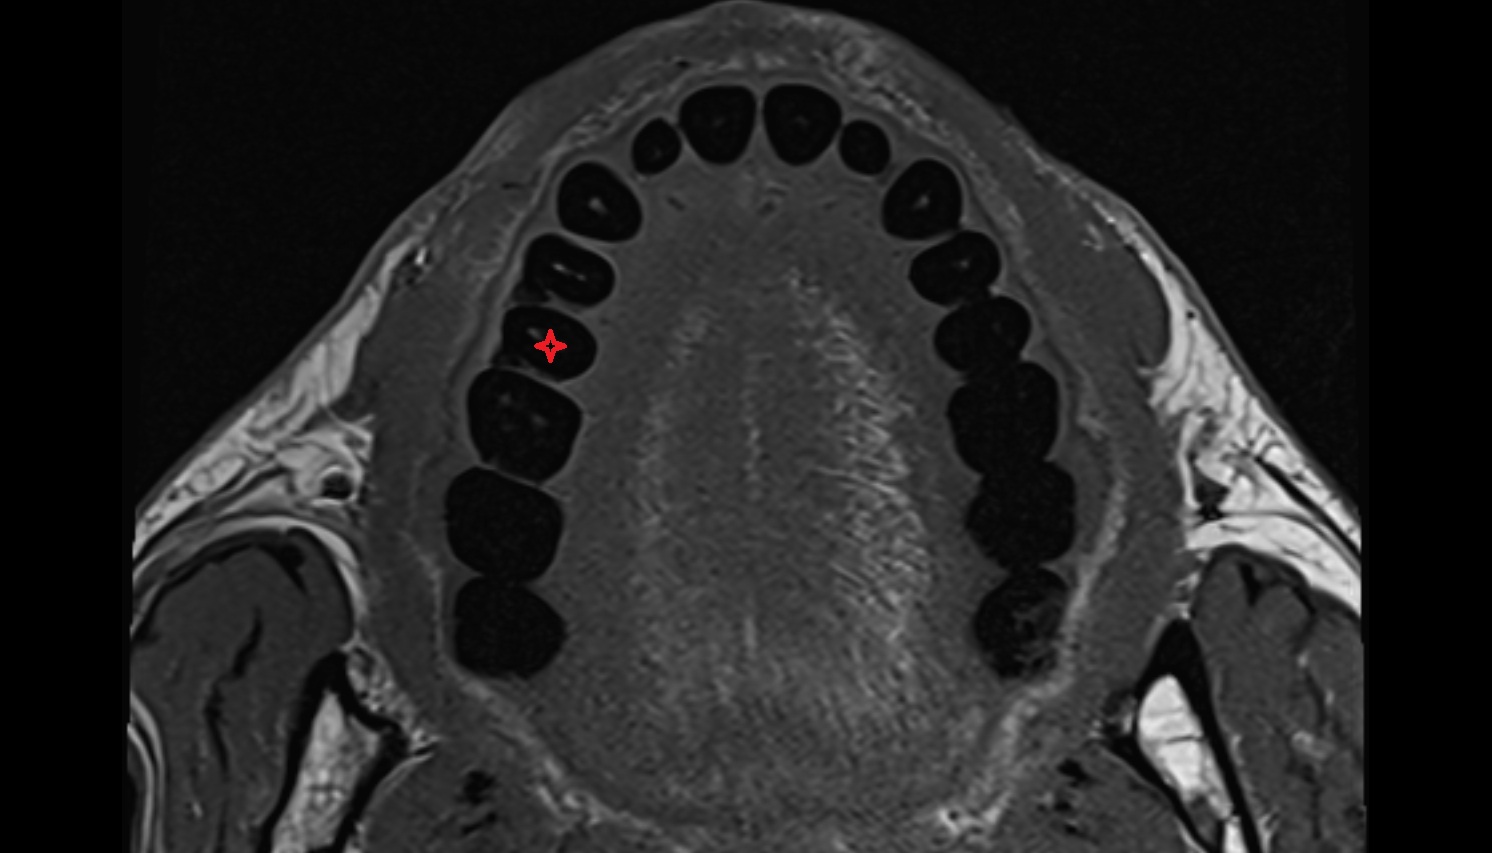

- Central inferior incisor tooth

- Central superior incisor tooth

- Inferior canine tooth

- Lateral inferior incisor tooth

- Lateral superior incisor tooth

- superior canine tooth

- Superior first molar tooth

- Superior first premolar tooth

- Superior second molar tooth

- Superior second premolar tooth

- Superior third molar tooth

- Inferior first premolar tooth

- Inferior second molar tooth

- Inferior second premolar tooth

- Inferior third molar tooth